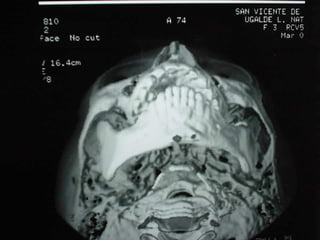

Radiografía

De Cara

24 horas de postoperatorio

24 horas depostoperatorio